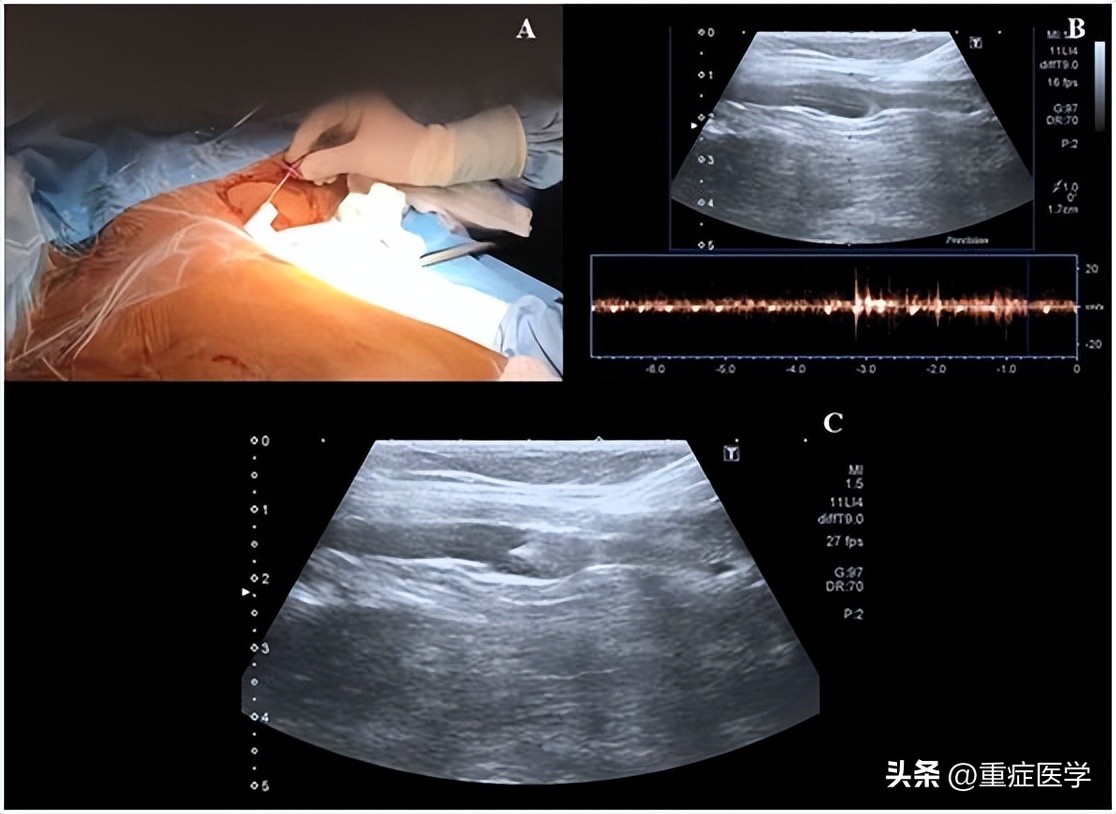

第三步,操作者左手持超声探头,右手持带穿刺针的注射器在超声引导下对腋静脉进行穿刺,超声长轴图像平面内同时可见静脉腔及穿刺针(图2)。皮肤穿刺点尽可能靠近超声探头远端的短边上。当穿刺针触碰到静脉前壁时,在压力的作用下,静脉壁会出现下沉塌陷,因此,此时应快速进针。

当在腋静脉腔内观察到针尖的斜面时(一个白点),可以很容易地确定穿刺针在血管内的位置(图2C)。也可以通过回抽血液1-2ml来确认穿刺针的位置是在静脉内。当患者血压较低时,无搏动性血流出现并不能排除穿刺到动脉的可能。随后置J形导丝,导丝的位置也可能在超声实时下确认(图3,A-C)。也可以通过颈部超声探查来排除导丝进行左侧颈内静脉。导丝置入长度应限定在20cm,以避免引起心律失常。随后扩张皮肤穿刺点,用Seldinger技术置入导管。在输注任何液体之前,回抽确认导管远端是否在血管腔内,随后再用肝素盐水冲洗导管。导管置入深度为20cm。

图2,A 沿超声探头长轴插入穿刺针;B 超声视窗下可见穿刺针进行静脉;C 超声视窗下看到的血管内穿刺针斜面。